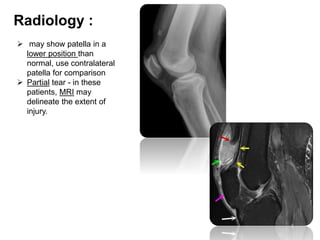

Radiology :

 may show patella in a

lower position than

normal, use contralateral

patella for comparison

 Partial tear - in these

patients, MRI may

delineate the extent of

injury.